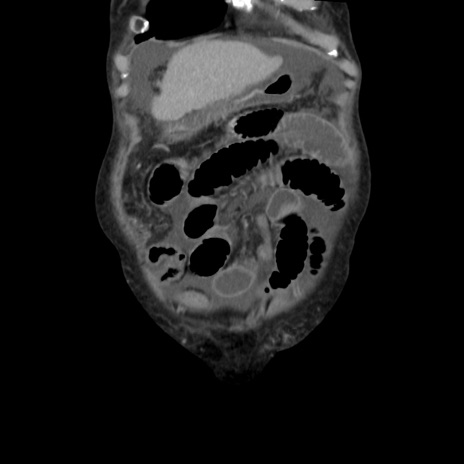

横断像

【症例】80歳代 女性

【主訴】腹部膨満感

【現病歴】他院にて肝硬変にてフォロー中。1週間前から便秘、腹部膨満感、臍部腫瘤あり受診となる。

【既往歴】肝硬変

【身体所見】腹部膨隆あり、皮膚変化なし、疼痛なし。

【データ】WBC 4600、CRP 0.25